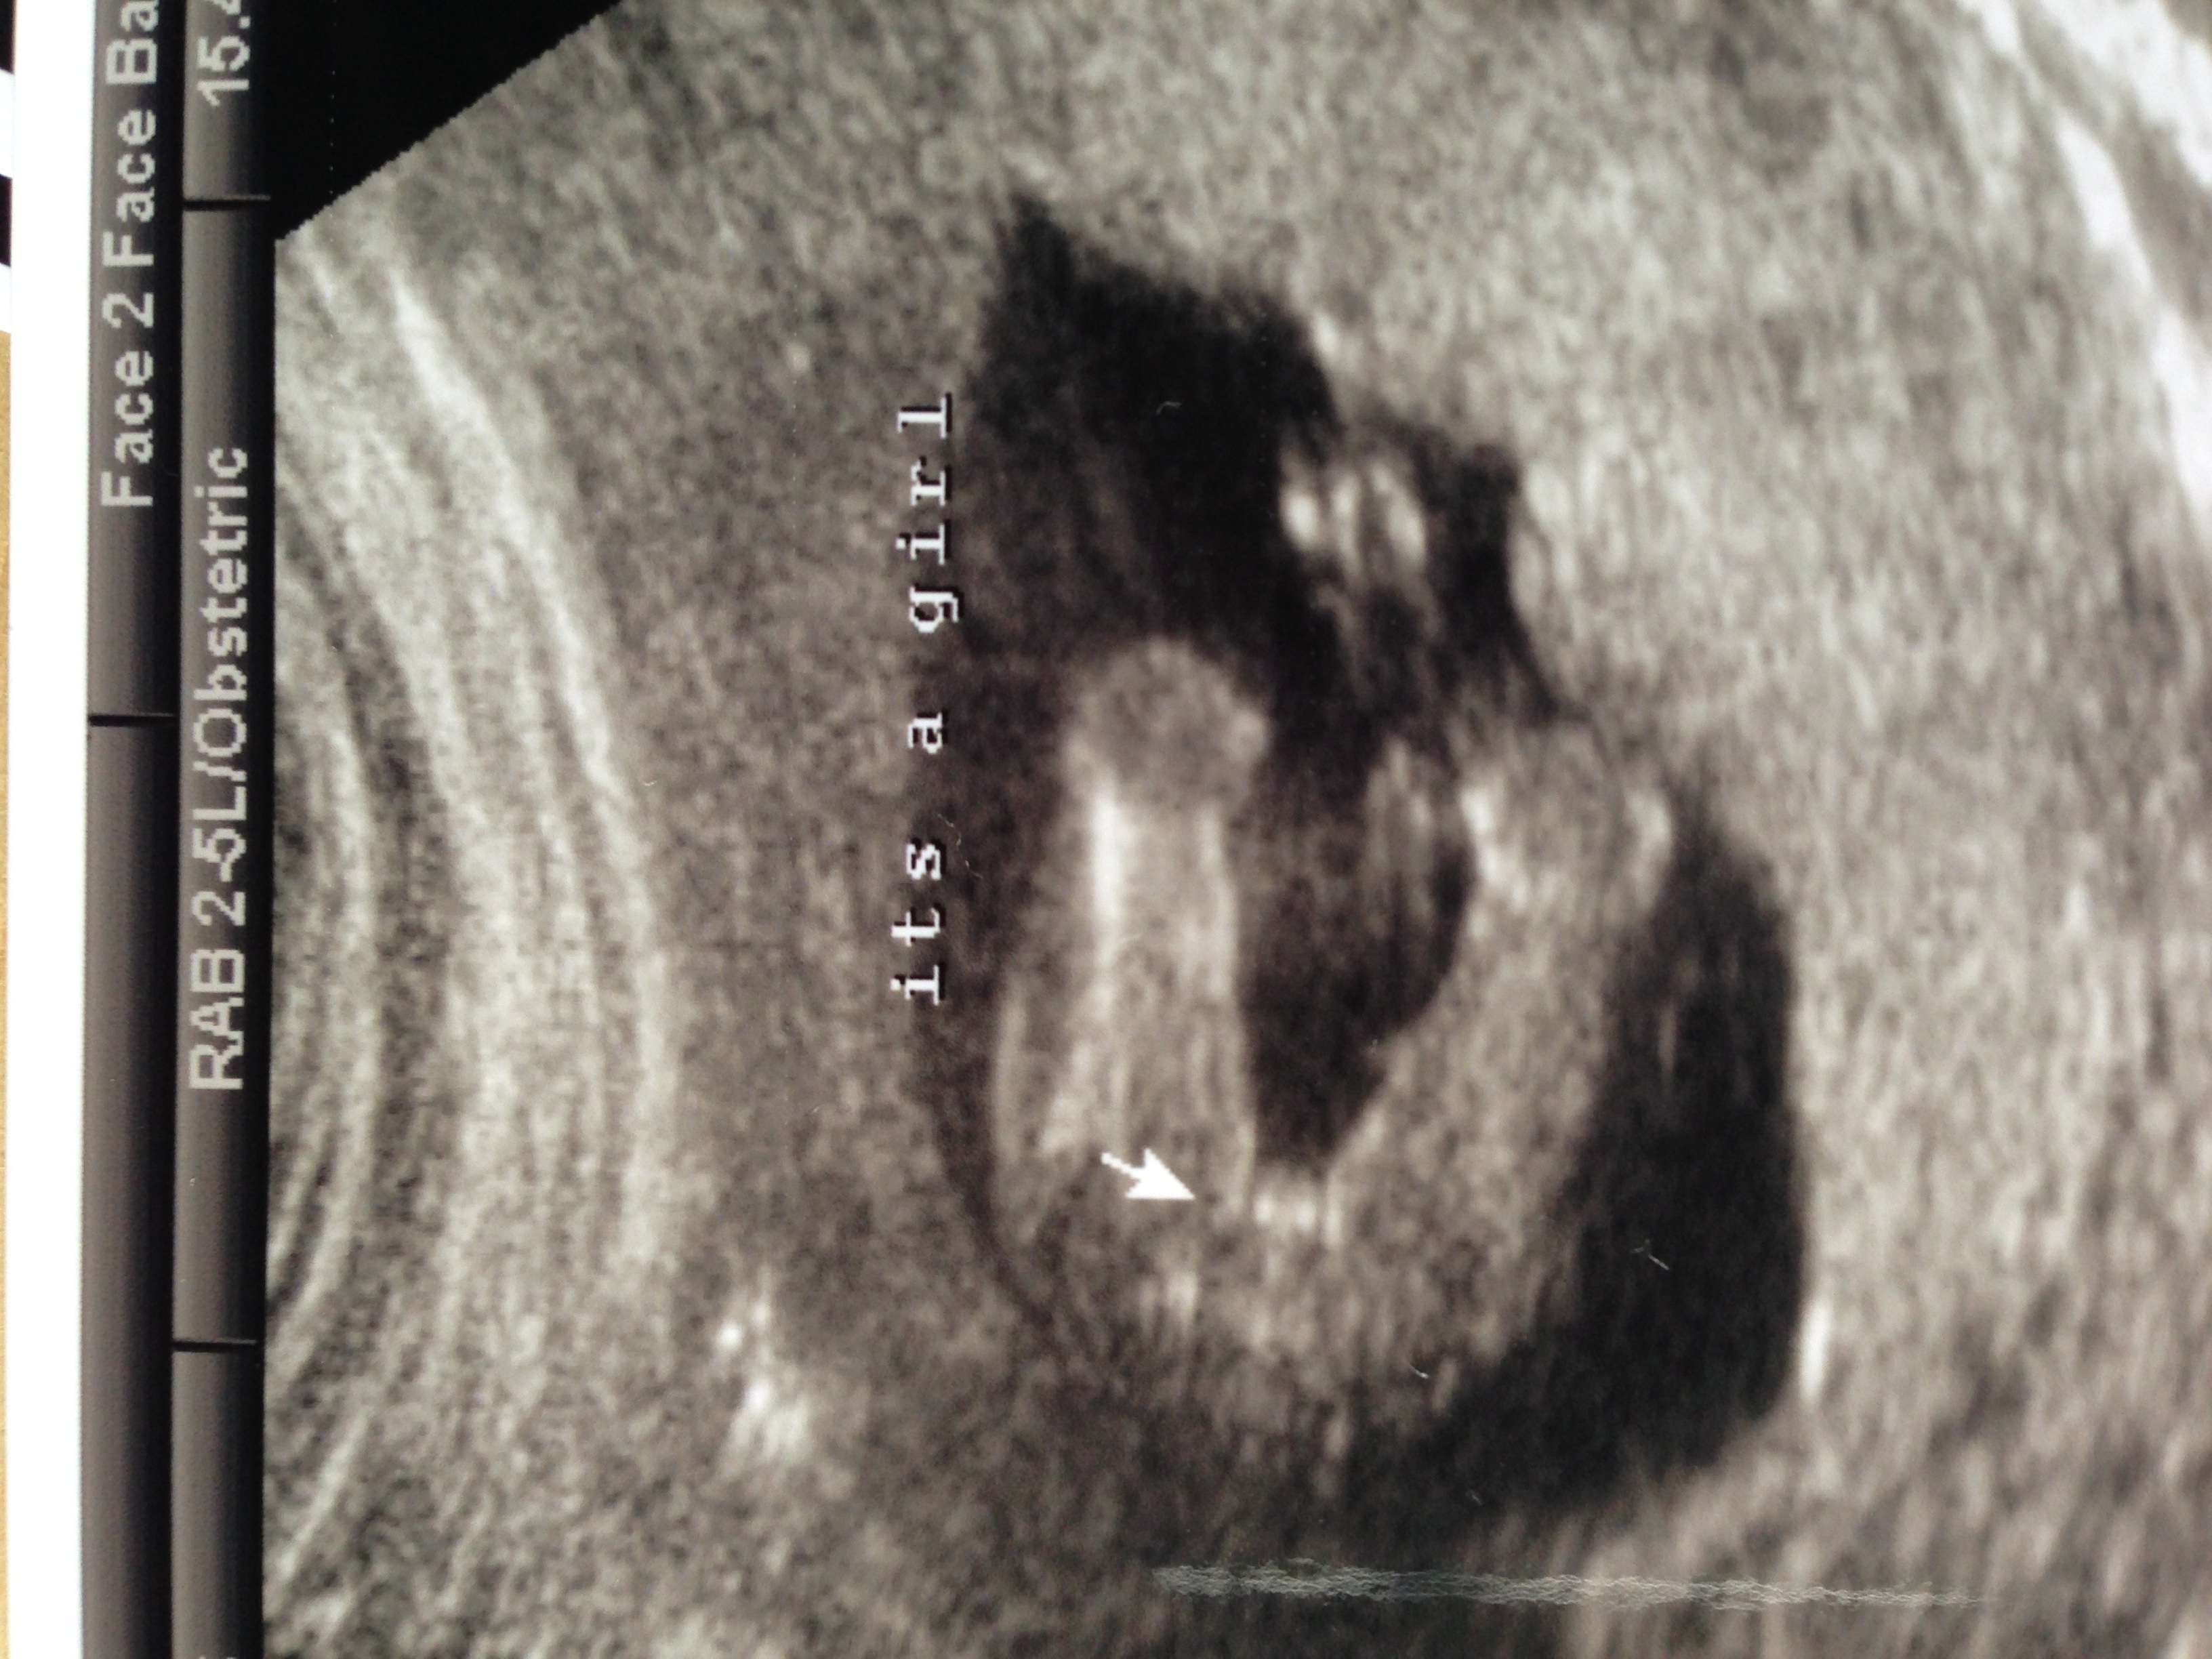

After all boy nub guesses was shocked to see girl parts and still trying to come to terms with it after being so desperate for a brother for my little girl.